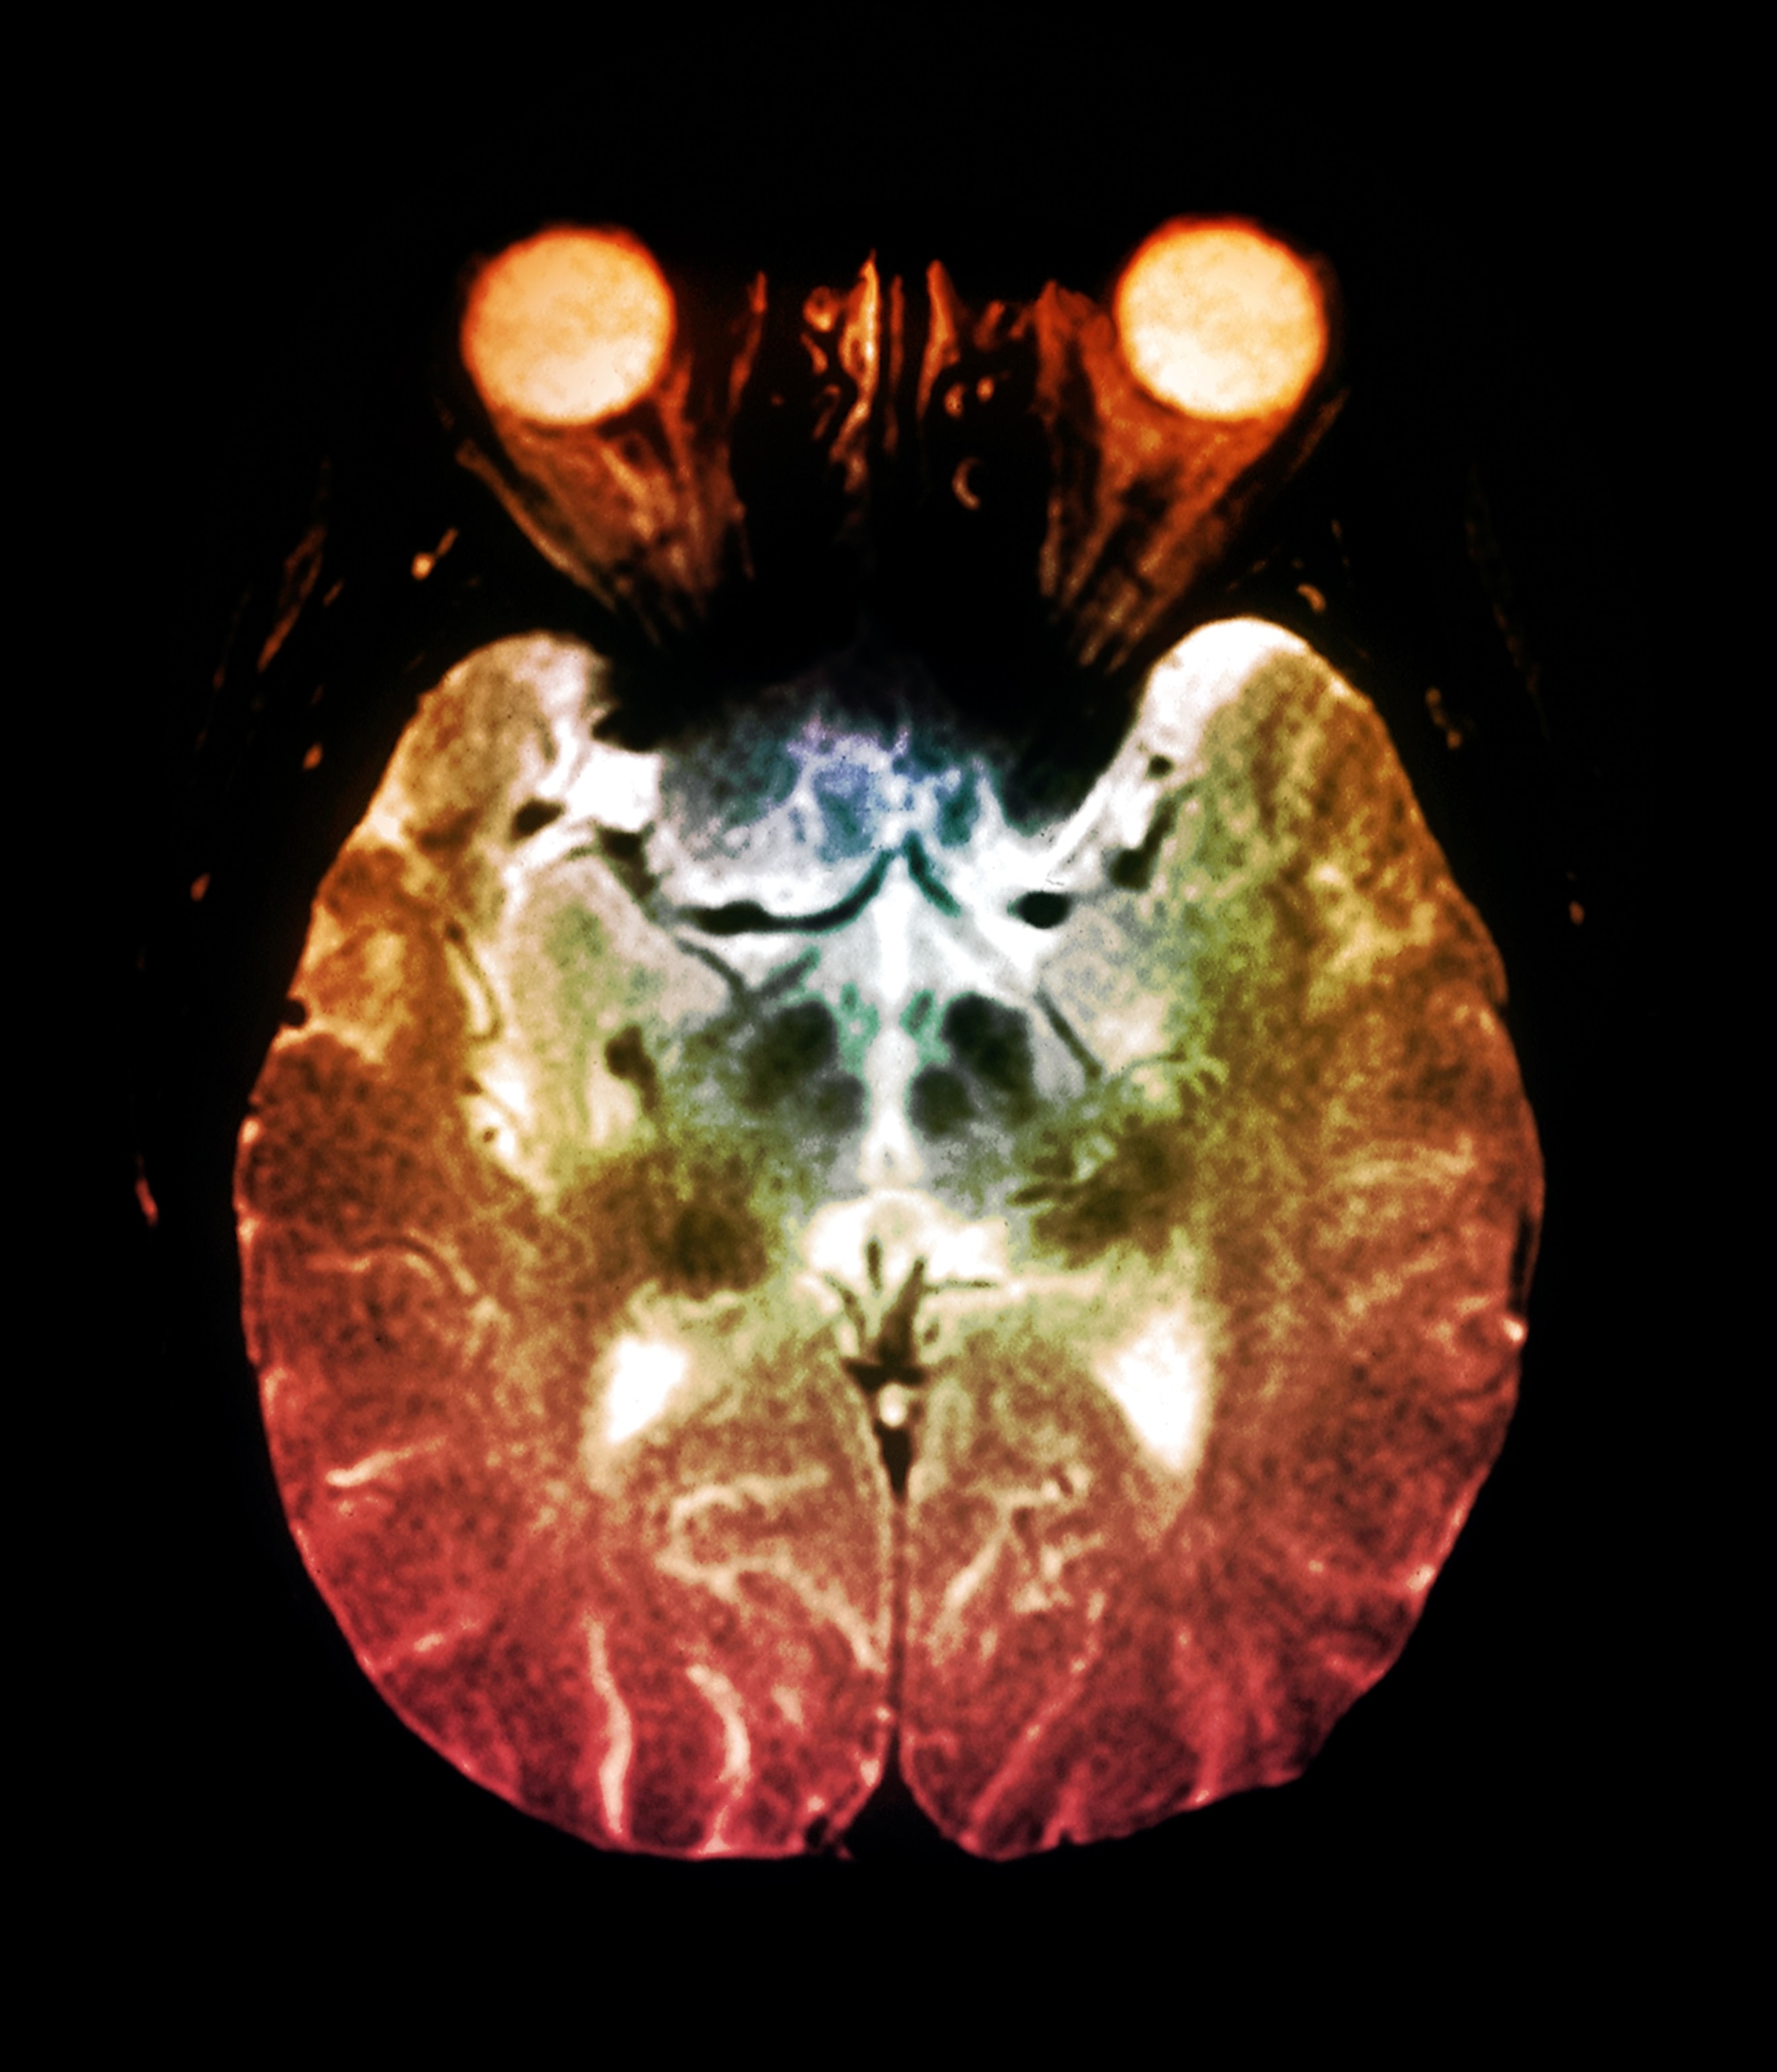

More than 10 million people worldwide are living with Parkinson’s disease, a progressive neurodegenerative disorder that leads to symptoms such as tremors, slow movement, limb stiffness, and balance issues. Scientists still don’t know what causes the disease, but it’s thought to develop due to a complex mixture of genetic and environmental factors, and treatment is still quite limited.

In a recent study published in JCI Insight, researchers found a common virus, called human pegivirus (HPgV), in the brains of patients who had Parkinson’s disease when they died. Although HPgV infections don’t usually cause symptoms, researchers believe the virus may be playing a role in the development of Parkinson’s.